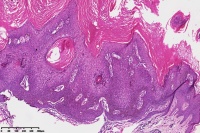

脂溢性角化症伴皮角?

女

年龄

49岁

手臂皮肤组织

图1

脂溢性角化病